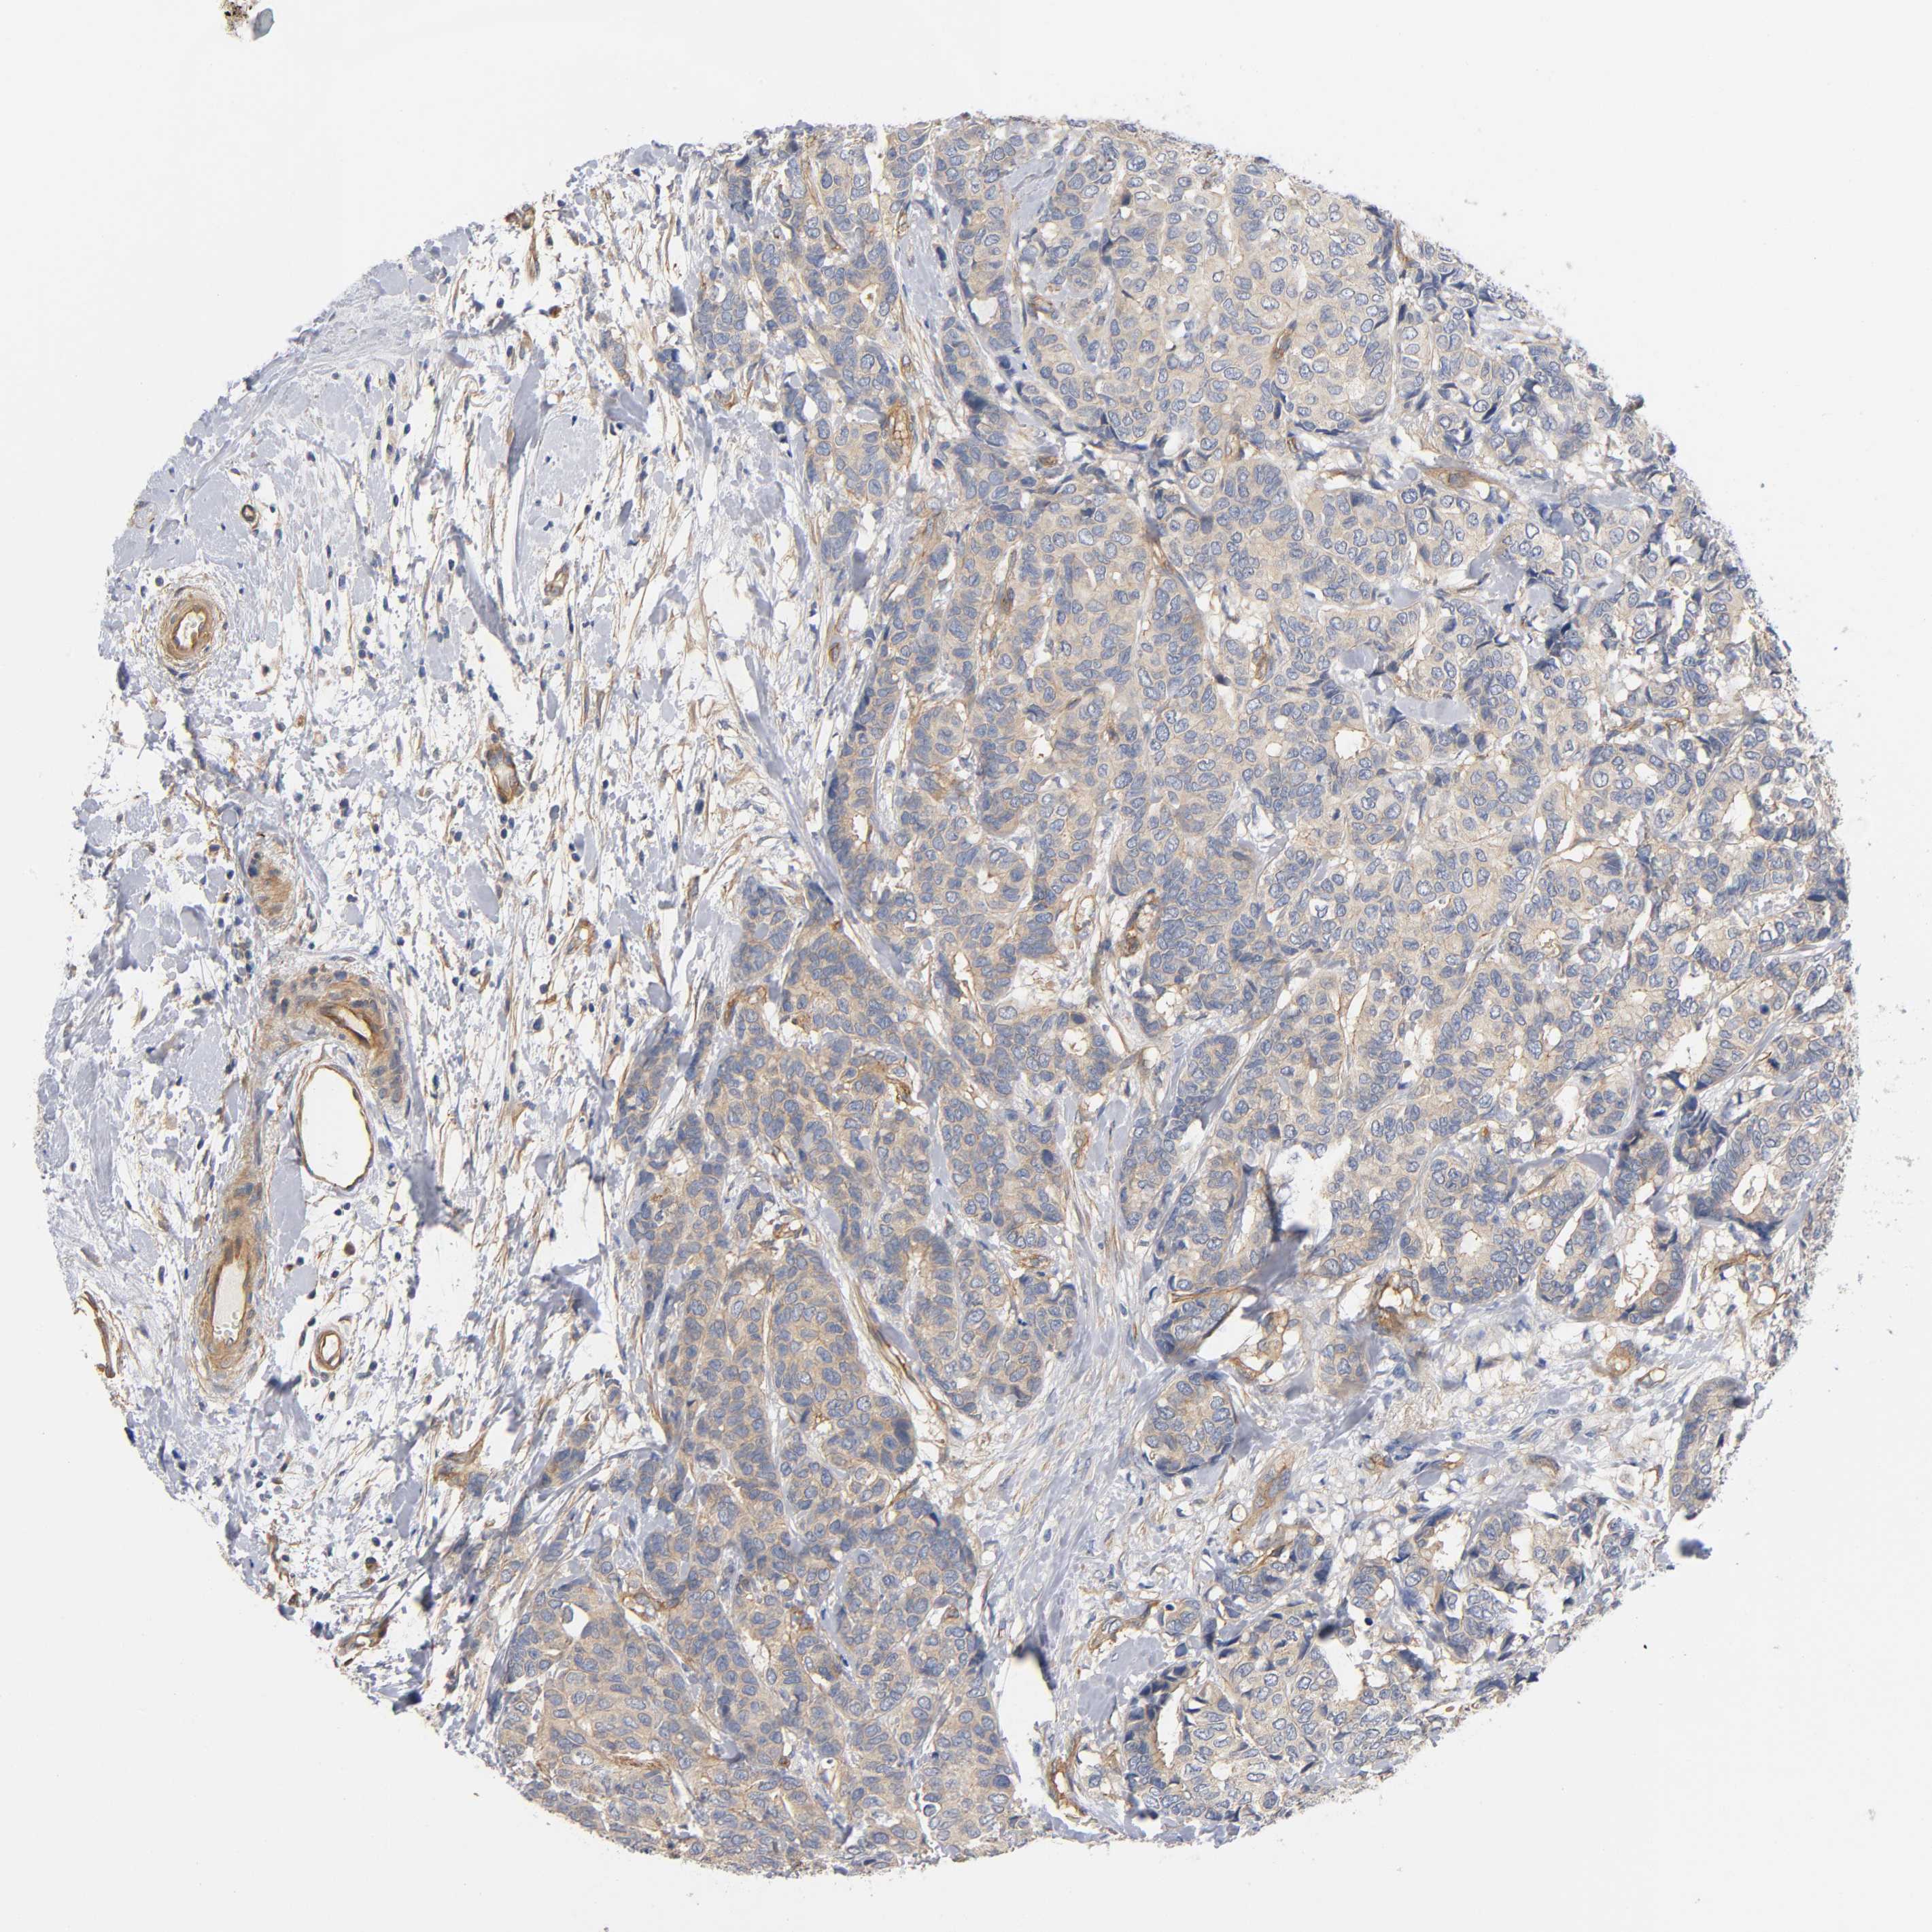

CANCER BREAST CANCER Show tissue menu

BRCA TCGA BRCA VALIDATION PROTEIN EXPRESSION

MARS1 is potential prognostic, high expression is unfavorable in Breast Invasive Carcinoma (TCGA)

Average pTPM 60.8

Number of samples 1022